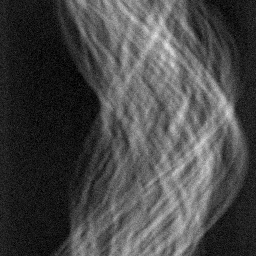

Figure 3: Qualitative completion results on TomoBank (lines 1 to 2) and LoDoPaB (lines 3 to 4) with random mask (ratio = 0.8) at 1024×\times1024 resolution. Odd columns and even columns show the sinograms and reconstructed images, respectively.

4.2.3 Completion Quality

Tab 2 summarizes accuracy results. At 2048×\times2048 resolution, HRSino achieves the best performance among all baselines while remaining memory-efficient, demonstrating its ability to extend high-quality completion to resolutions where other diffusion models fail. At 1024×\times1024, HRSino delivers accuracy comparable to its computation-intensive counterpart RePaint, showing that our optimizations do not compromise fidelity at moderate scales. Compared to DiffIR, MCG, TD-Paint, and HiDiffusion, HRSino consistently achieves higher SSIM and PSNR across mask ratios, with improvements up to +0.03 SSIM and +1.8 dB PSNR. Fig 3 visualizes sinogram completion and reconstructed images, where HRSino produces nearly indistinguishable results from RePaint. These findings confirm that HRSino fundamentally extends diffusion-based completion to 2048×\times2048 resolution in a more memory- and runtime-efficient manner.